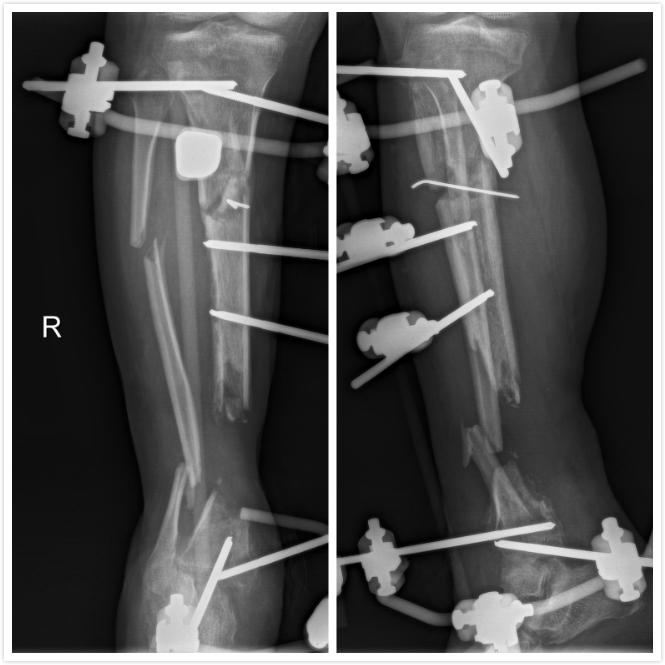

▲外院清创固定术后图

徐杨主任医师、许春财副主任医师在全面评估后,考虑小罗右小腿虽然皮肤肌肉溃烂、缺损,胫骨大段缺损,合并严重多重耐药菌(MRSA)感染,血管神经也均有较严重损伤,但残留胫后血管尚能维持远端血供,这将是小罗保住右腿的一线希望!